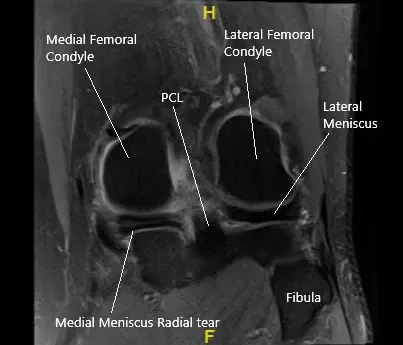

Resonancia magnética de la rodilla izquierda en la sección coronal que muestra el menisco medial desgarrado.

La resonancia magnética de la rodilla izquierda sugirió una ruptura del menisco medial del cuerno posterior, especialmente con un componente radial en el tercio interno, con extrusión meniscal hacia la canaleta medial. Hay artrosis tricompartimental, más pronunciada sobre el compartimento patelofemoral. Tendinosis del mecanismo extensor. Tendinosis insertional semimembranosa.